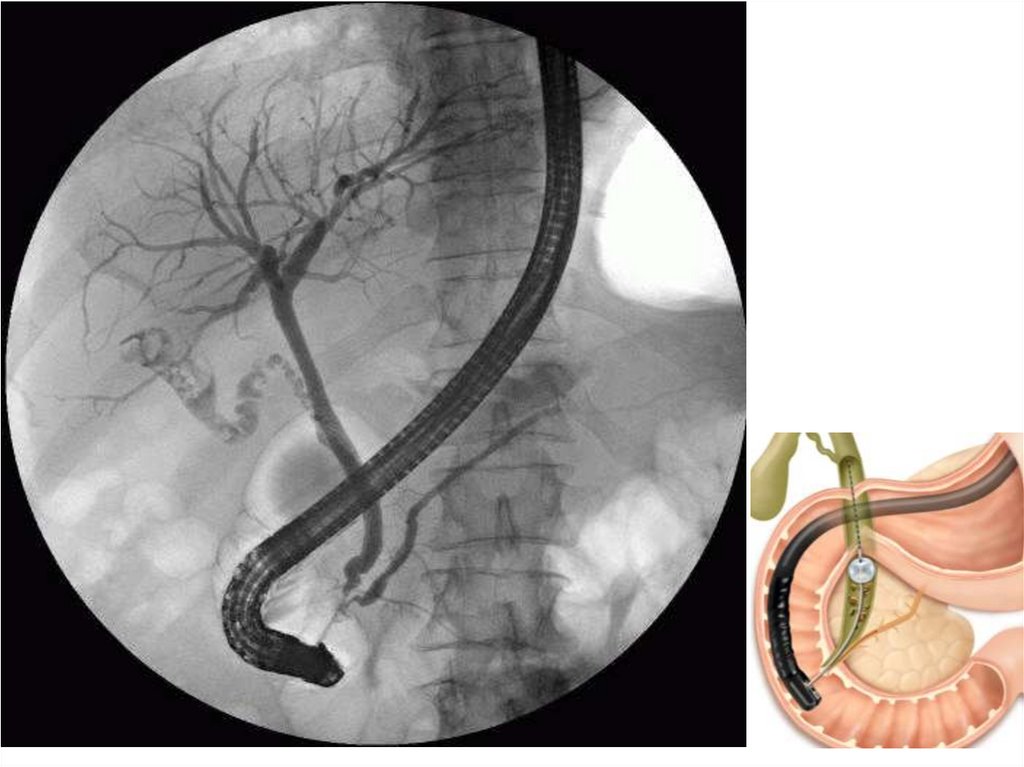

Видео ЭРХПГ, ЭПСТ, Литоэкстракция. 02:10 и далее на быстрой промотке

44. Видео ЭРХПГ, ЭПСТ, Литоэкстракция. 02:10 и далее на быстрой промотке

• https://www.youtube.com/watch?v=x9OceQh

cg-I